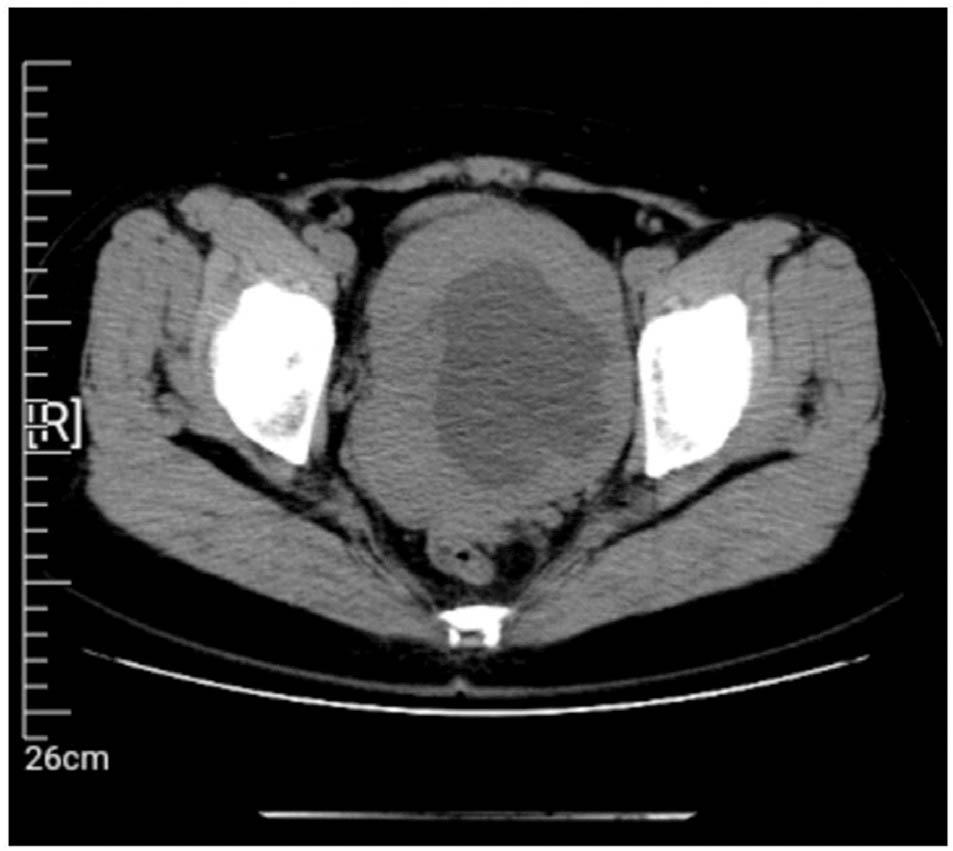

Figure 1

Pelvic computed tomography image showing an unclear defined 11 cm pelvic mass without further abnormalities.